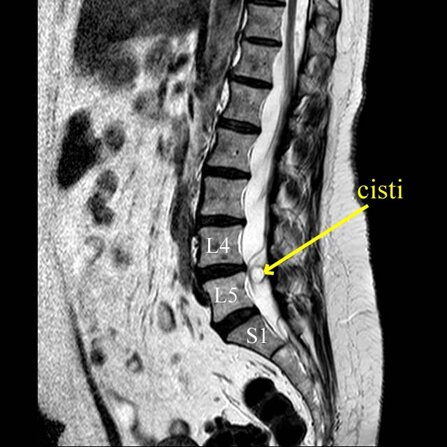

Una risonanza lombare ha evidenziato cisti sinoviale a ridosso della radice nervosa a livello L4-L5 sinistra.

Non presentava disturbi di forza all’esame neurologico obbiettivo.

Optava per ozonoterapia.

Nel corso delle sedute (effettuate alcunecon tecnica ecoguidata iuxtaradicolare L4-L5 graduale diminuzione del dolore sciatico.

Alla fine delle 8 sedute (4 settimane di trattamento), regressione completa del dolore alla gamba sinistra, con possibilità completa di mobilizzazione e graduale ritorno alla normalità.

A distanza di 4 mesi ha effettuato una nuova risonanza magnetica lombare, che ha documentato la completa scomparsa della cisti sinoviale.

Anche in questo caso non è dimostrabile l'esclusivo rapporto tra ozonoterapia ecoguidata e la scomparsa della cisti sinoviale.